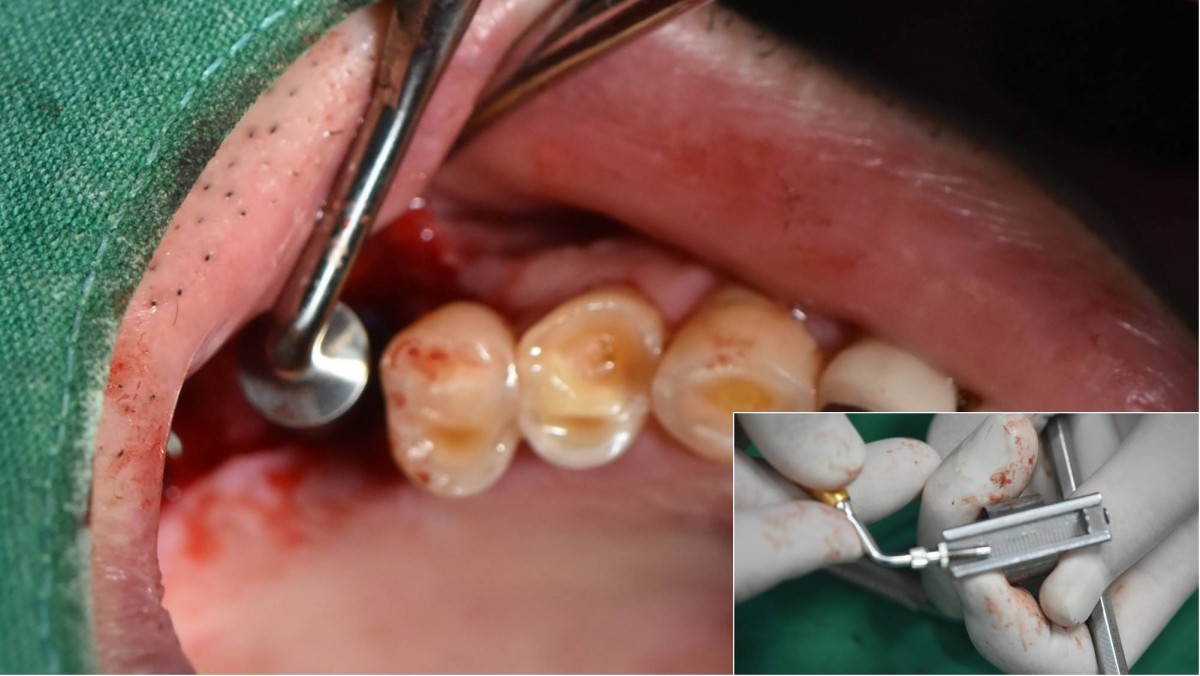

Socket Lift and Implant Placement in the right maxilla.

<GCacg> A 56-year-old male patient complained of pain in the right upper and lower jaws. And he wanted the upper first molar to be pulled out first.